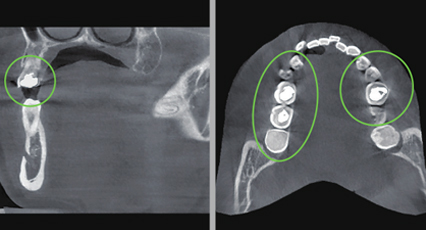

通过气道分析功能对比矫正患者的治疗前后变化。

VATECH已经打破了许多牙科影像的惯例。人们一直认为,金属伪影会导致劣质的影像质量,然而这问题始终无法解决。现在,ART-V可以有效减少金属伪影,使得图像质量更有诊断价值。